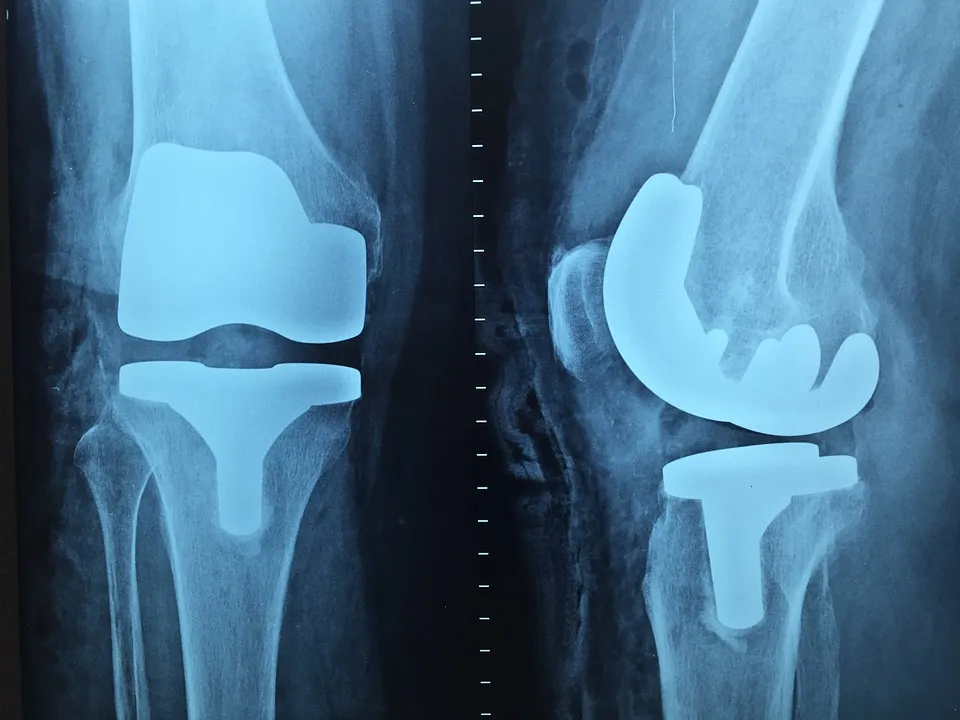

De gemeente is blij met het initiatief van de Reinier Haga Groep om op korte termijn in het Lange Land Ziekenhuis een orthopedisch centrum te bouwen.

Hierdoor kan het ziekenhuis zich duurzaam ontwikkelen en blijft ziekenhuiszorg in Zoetermeer ook in de toekomst gegarandeerd.